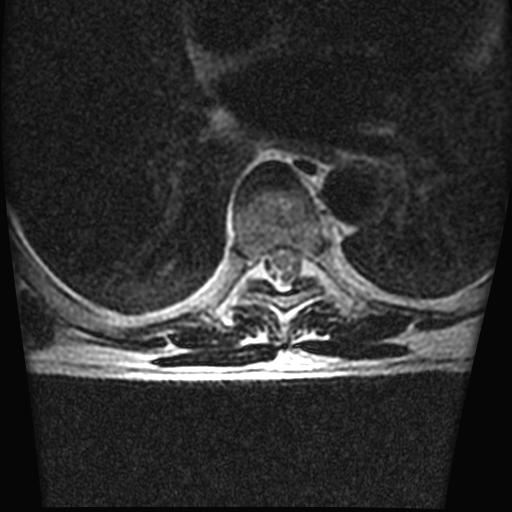

68岁男性,胸部疼痛,不适。

胸7椎体楔状变形及信号异常,附件未见明显异常信号.椎间隙正常.未见软组织块影.考虑骨质疏松所致压缩性骨折可能大.

胸7椎体楔状变形及信号异常[t1t2 均为低信号],附件未见明显异常信号.椎间隙正常.未见软组织块影.考虑陈旧性压缩性骨折伴退变。

首先需除外单发成骨性转移瘤可能。

转移瘤也不能排除